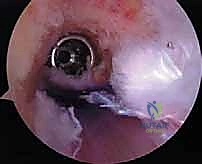

- الجراحة المجهرية وتنظير المفاصل بدقة 4K: يستخدم الدكتور هطيف أحدث تقنيات مناظير الركبة (Arthroscopy) المزودة بكاميرات عالية الدقة 4K، مما يتيح له رؤية أدق التفاصيل داخل المفصل، وتشخيص الأضرار المجهرية، وإجراء الجراحة بأقل تدخل جراحي ممكن (Minimally Invasive).

* التصوير بالرنين المغناطيسي (MRI): يوفر صورة مفصلة للأنسجة الرخوة. يحدد حالة الطعم المزروع سابقاً (هل هو ممزق، متآكل، أم سليم ولكنه غير فعال؟)، ويقيم حالة الغضاريف الهلالية والمفصلية.